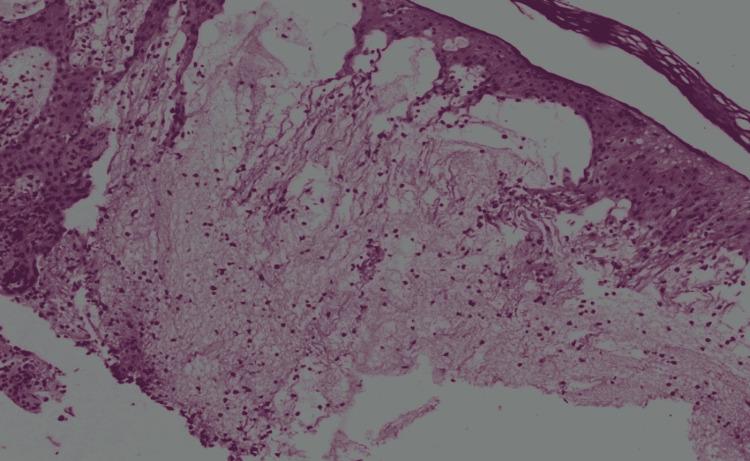

As more people come into contact with seawater and freshwater bodies each year, medical providers are increasingly likely to encounter cases of aquatic dermatitis. The cutaneous manifestations caused by marine organisms can range from a pruritic, macular rash to a painful, vesicular eruption. Some conditions, such as those resulting from jellyfish envenomation, present with a distinct pattern allowing precise diagnosis and treatment. However, other conditions, such as swimmer's itch, may cause vague dermatitis, making diagnosis more challenging. Determining the etiology can aid in the overall management and treatment of these patients.